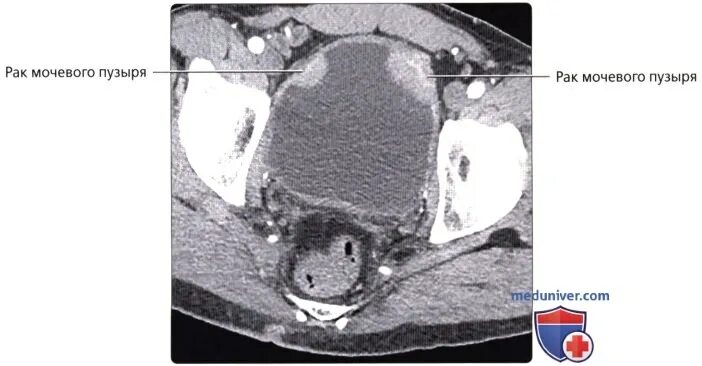

Уплотнение стенки мочевого пузыря